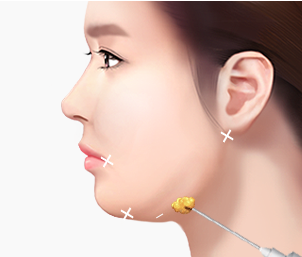

BUCCAL FAT REMOVAL

심부볼지방제거

심부볼지방제거는 볼 안쪽 깊숙이 위치한 지방 덩어리를 제거하여

둥글고 통통한 얼굴을 갸름하고 세련된 V라인으로 만드는 수술입니다.

입안을 절개하여 외부 흉터가 전혀 없으며

영구적인 소얼굴 효과를 얻을 수 있습니다.

웃을 때 불룩한 볼,

갸름한 V라인으로 개선합니다

심부볼은 볼 안쪽 깊숙이 위치한 지방 덩어리로

피하지방과는 달리 다이어트로는 빠지지 않는 고유한 구조물입니다.

심부볼의 위치

볼 안쪽 깊은 곳에 위치

심부볼의 특징

다이어트로 빠지지 않는 지방

제거 시 효과

갸름한 V라인 완성